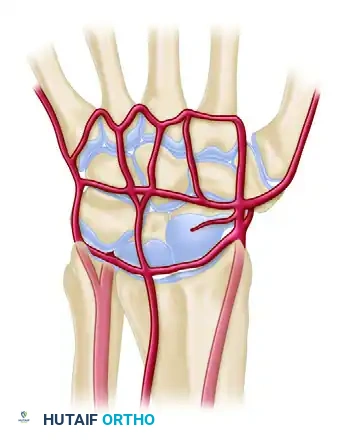

Vascular Anatomy and Circulation

The extraosseous blood supply to the carpus is derived from the terminal branches of the radial, ulnar, and anterior interosseous arteries. These form a highly redundant network of three dorsal and three palmar transverse arterial arches.

Dorsal Arterial Arches

- Dorsal Radiocarpal Arch: Located at the radiocarpal joint; supplies the proximal poles of the scaphoid, lunate, and triquetrum.

- Dorsal Intercarpal Arch: The largest dorsal arch, located between the proximal and distal rows. It supplies the distal carpal row and anastomoses with the radiocarpal arch.

- Basal Metacarpal Arch: Highly variable; supplies the distal carpal row and carpometacarpal joints.

Palmar Arterial Arches

- Palmar Radiocarpal Arch: Supplies the palmar surfaces of the lunate and triquetrum.

- Palmar Intercarpal Arch: Highly variable; rarely contributes significant nutrient vessels to the intraosseous carpus.

- Deep Palmar Arch: Consistent and robust; communicates directly with the dorsal basal metacarpal arch.

Clinical Pearl: The scaphoid and lunate rely heavily on retrograde intraosseous blood flow. The scaphoid receives 70-80% of its blood supply via dorsal ridge vessels entering distally, making proximal pole fractures highly susceptible to avascular necrosis (AVN) and nonunion.